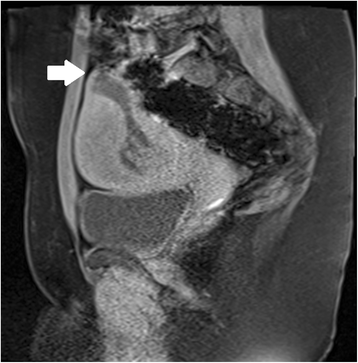

Ultrasound criteria for diagnosis of an interstitial ectopic pregnancy include a gestational sac at least 1 cm lateral to the edge of the uterine cavity, with a thin (5 mm or less) layer of overlying myometrium surrounding it (Figs. 3 and 4) [99, 100]. An ‘interstitial line’ may also be seen (Fig. 5) [101].

Interstitial ectopic pregnancy by transvaginal ultrasound. The arrow indicates thin (<5 mm) myometrium overlying the ectopic pregnancy. This finding by ultrasound, in combination with the lateral location of the gestation, has a reported specificity of 88-93 % but a sensitivity of just 40 % [101].